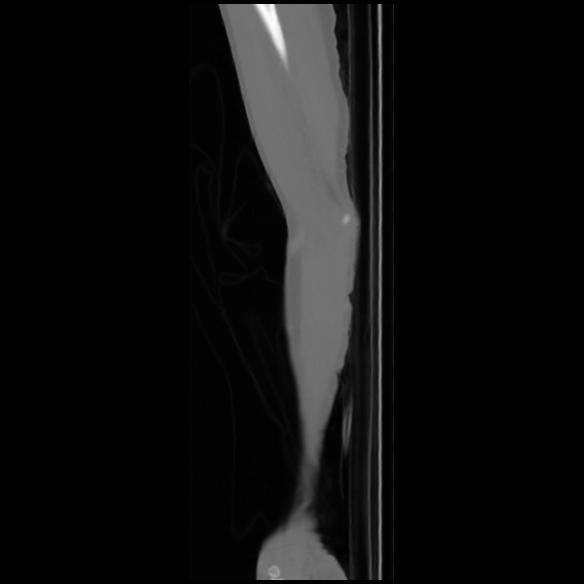

7 CUERPO,CE,Sagittal,3.000,CUERPO,Sagittal,